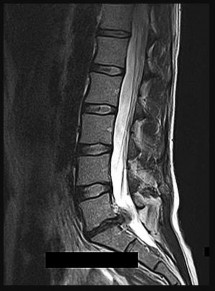

Question 6:

During a primary posterior-stabilized total knee arthroplasty, the surgeon assesses the flexion and extension gaps. The knee is found to be tight in both extension and flexion. Which of the following surgical adjustments is the most appropriate next step?

Correct Answer: Resect more proximal tibia

Explanation:

In gap balancing for total knee arthroplasty, the proximal tibial cut affects both the flexion and extension gaps equally. If the knee is symmetrically tight in both flexion and extension, resecting more proximal tibia (or using a thinner tibial polyethylene insert) will increase both gaps equally. Resecting more distal femur would only loosen the extension gap. Changing the femoral size primarily affects the flexion gap (downsizing loosens flexion; upsizing tightens flexion).